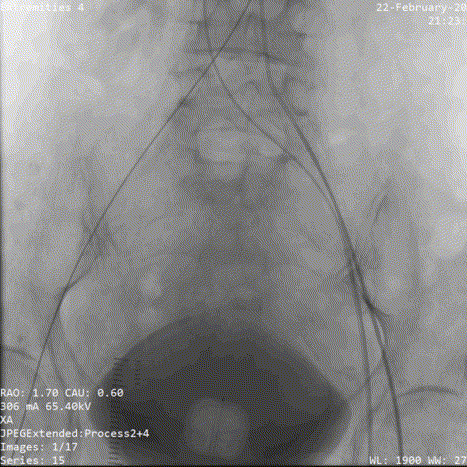

术中影像:

1.确认共平面

2.初始定位